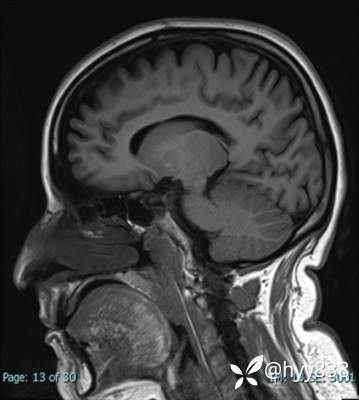

MRI sag T1WI + axi T2WI+FLAIR